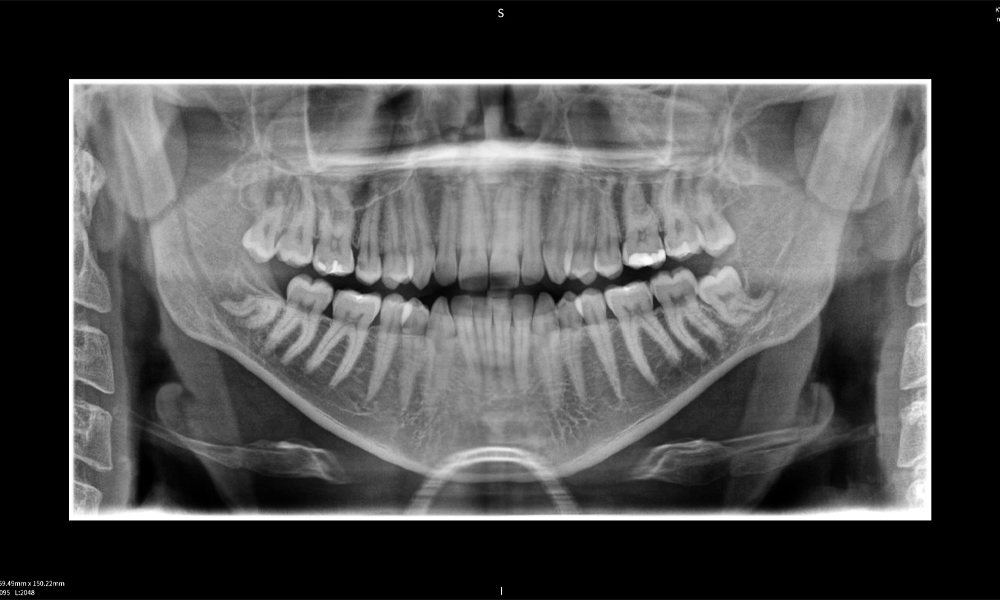

Figure e: Imaging results of Seethrough Max, in front of a black background.

Figure e

Figure e: The panoramic X-ray serves as an initial assessment tool, showing the general positioning of the teeth as well as any potential pathological changes. Notably, on the right side (tooth 48), the situation following a crown amputation performed by an external practitioner is visible. The two severely curved roots remain in close topographical proximity to the inferior alveolar nerve within the bone. This suggests a deliberate decision to avoid the increased risk of nerve injury during a complete extraction, and represents a clinically relevant finding. In summary, CBCT scans with Seethrough Max, provide crucial information about the complex anatomy and the critical relationship between the wisdom teeth and the inferior alveolar nerve. This detailed preoperative diagnostic imaging is essential for safe and successful surgical procedures in the mandibular region.